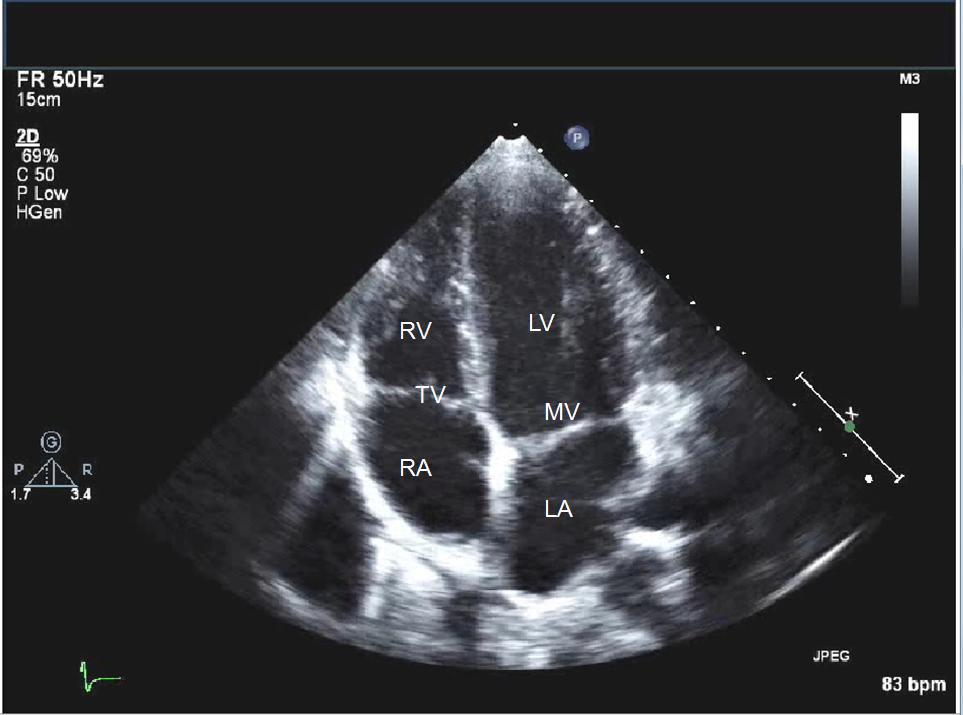

work Object Detection in Cataract Surgical Images Object detection in cataract surgery images using YOLOv5 to monitor intraoperative deviations. Classification of Surgeon Skill Level Classifying surgeon skill levels from cataract surgical videos using V-JEPA and LSTM Models. Converting Handwritten Mathematical Equations to LaTeX Code Designed a system using image processing and CNNs to convert handwritten equations into LaTeX code. Mid-diastole Frame Detection using Echocardiography Images Applied image processing and ML algorithms to detect mid-diastole frames in echocardiography for mitral valve stenosis diagnosis. fun